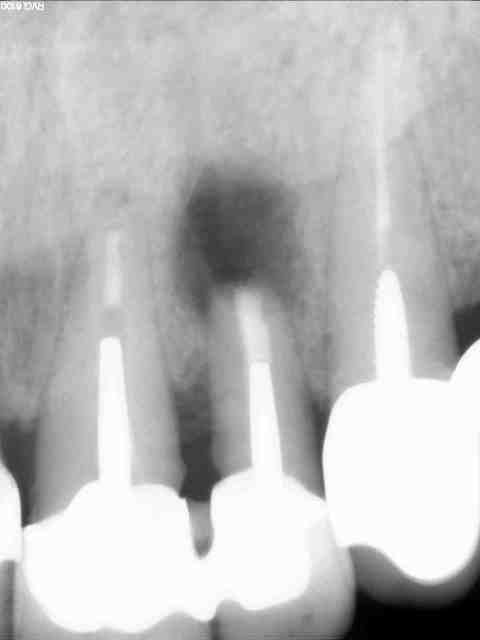

Pas trop nul à chier pour une fois :-)

Obturation a retro au MTA, beta TCP en comblement (plus de corticale osseuse vestibulaire). C'est un choix qui se discute, mais si certains ont des remarques constructives...je prend.

Salut, est-ce que tu n'as pas peur qu'il y ait des problèmes d'étanchéité coronaire (reprises de carie ?) dans ce cas sur la dent traitée ainsi que sur la dent d'à côté (dont l'apex n'est pas bien net non plus) ?

Les couronnes (solidarisées semble-t-il) sont inadéquates.

Il me semble que le comblement soit bien fait (j'aurais aussi comblé), mais

il n'y a pas encore de guérison osseuse.

C'est un futur cas d'implant....

1)manque d'étanchéité coronaire

2)ton rapport couronne racine est totalement défavorable heureusement que les ccm sont solidarisées

3)ton atteinte en mésiale remonte plus haut que ta résection.

tu as bien fait de combler pour le clou qui sera peut être à envisager.

Plus sérieusement, je vous trouve assez sévère avec l'étanchéité des couronnes. Certes, elles ne sont pas parfaites. Il y a des encoches en mésiale de 22 et distal de 21...due au passage de brossette. Il n'y a absolument pas de reprise carieuse. Ce qui, je suis d'accord aurait contre-indiqué la chirurgie en première intention.

> 3)ton atteinte en mésiale remonte plus haut que ta résection.

C'est vrai. J'ai passé du temps avec mon insert à nettoyer cette zone (et tout autour d'aileurs, notamment en palatin).

> tu as bien fait de combler pour le clou qui sera peut être à envisager.

Si ça permet ça, ce sera déjà pas mal. JY Cochet a montré à l'ADF de l'année dernière des cas sur secteur postéro-inférieur où le but était justement de regagner de l'os pour l'implant.